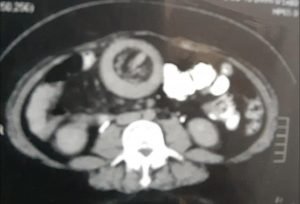

إستخدام المنظار الجراحي لعلاج إنسداد بالأمعاء الدقيقة نتيجة إنغماد جزء من الأمعاء الدقيقة(الصائم) في جزء آخر

Laparoscopic surgery for Jejuno-Jejunal intussusception